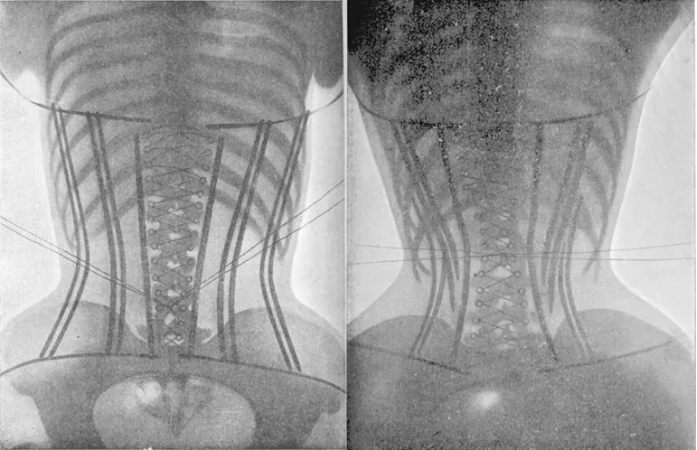

Una Faja Colombiana Es Igual Que Usar Un Cinturón Para Levantar Pesas

Estas fajas o “entrenadores de cintura” son muy diferentes al uso del cinturón para levantar pesas.

Las fajas son usadas por personas (especialmente mujeres) que quieren estrechar su cintura a como dé lugar.

Las diferencias entre el uso de fajas colombianas y los cinturones para levantar peso son 2:

las fajas están tan apretadas (para que puedan estrechar las costillas, haciendo ver la cintura más pequeña) que obstaculizan la respiración

las fajas se utilizan por mucho tiempo a lo largo del día

Sobre estos aspectos, la American Board of Cosmetic Surgery, menciona que llevar puesta estas fajas puede reducir la capacidad pulmonar entre un 30-60%12.

Así lo han demostrado también otros estudios 13.

Incluso, pueden disminuir la circulación de la sangre que llega a los dedos en un 36%14.

Esto es un problema, porque todos hemos visto a mujeres utilizar estas fajas mientras se ejercitan en el gimnasio, provocando que no tengan una oxigenación suficiente cuando más lo necesitan.

Además, el efecto de estos entrenadores de cintura no es saludable.

Esto debido a que, si logran deformar la estructura de tus costillas para crear una cintura más pronunciada, van a modificar de forma permanente la posición de algunos de tus órganos…

fajas colombianas reductoras efectos secundarios

Esto, como puedes imaginarte, no es saludable en lo más mínimo.

Cuando tomas una faja y la aprietas a más no poder contra tu zona abdominal durante mucho tiempo es obvio que va a apretar también a tu sistema digestivo.

Tu esófago, estómago, y tus intestinos pueden ser afectados.

Por ejemplo, la presión ejercida en tu estómago puede provocar que tengas reflujo gástrico.

También puede afectar al diafragma, hígado y riñones.

fajas colombianas

Las fajas ejercen una presión que no es natural para tu cuerpo, y eso puede hacer que algunos órganos reciban menor flujo sanguíneo al estar contraídos.

Esto puede afectar su función.

En cambio, el cinturón para levantar peso, no aprieta tu cintura de forma constante, sino que crea algo de resistencia al momento de que tomas una bocanada de aire.

Esto crea presión intraabdominal sin ejercer modificación alguna a tus huesos y órganos.

Y esta presión termina al momento de que completas cada serie.